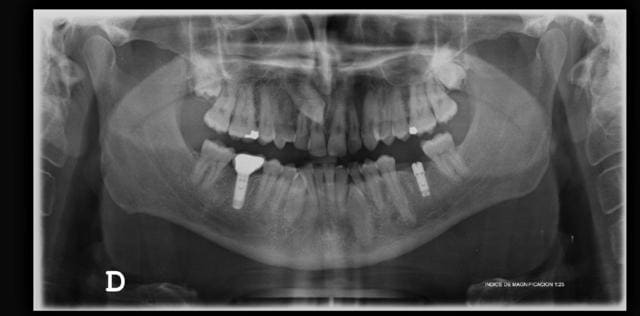

Bonjour,

De quel implant s'agit-il en 46?

Le patient se plaint de douleurs à la mastication non permanentes sur cette couronne. je ne vois rien sur la rx et rien à l'examen buccal....Une idée?

petit détail, c'est une couronne transvissée.

Y'aurait pas un sd du septum par intermittence en mésial?

La couronne n'est-elle pas compressive en distal (peu d'espace avec le rebord osseux sur la panoramique)?

La compression en distal et le sd du septum j'y crois pas trop, car la couronne est en place depuis 10 ans et c'est apparu récemment. La gencive n'est pas enflammée, jamais de signements.

Peut être une fracture/fissure de l'implant ou au niveau de la connexion?